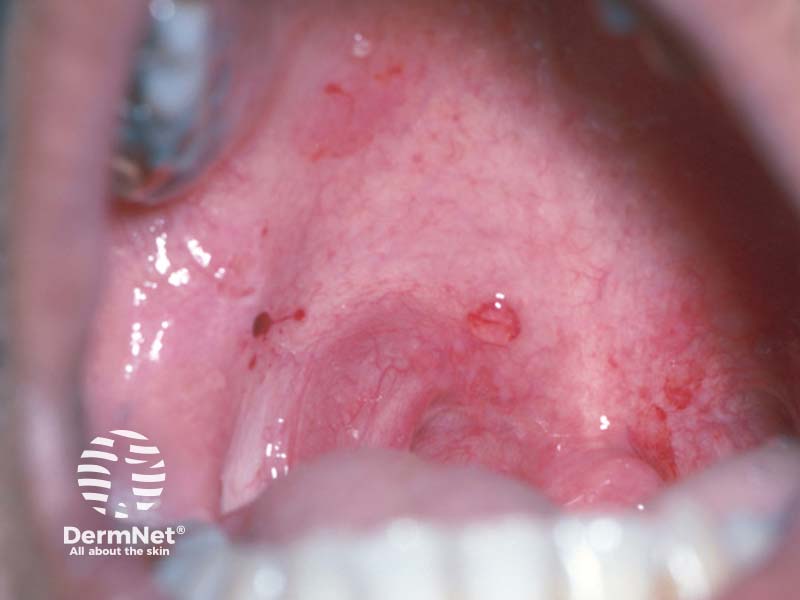

A cluster of oral ulcers

Oral ulcers and new skin blisters